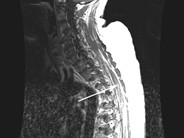

Granulocytic sarcoma in a patient with Acute Promyelocytic Leukemia